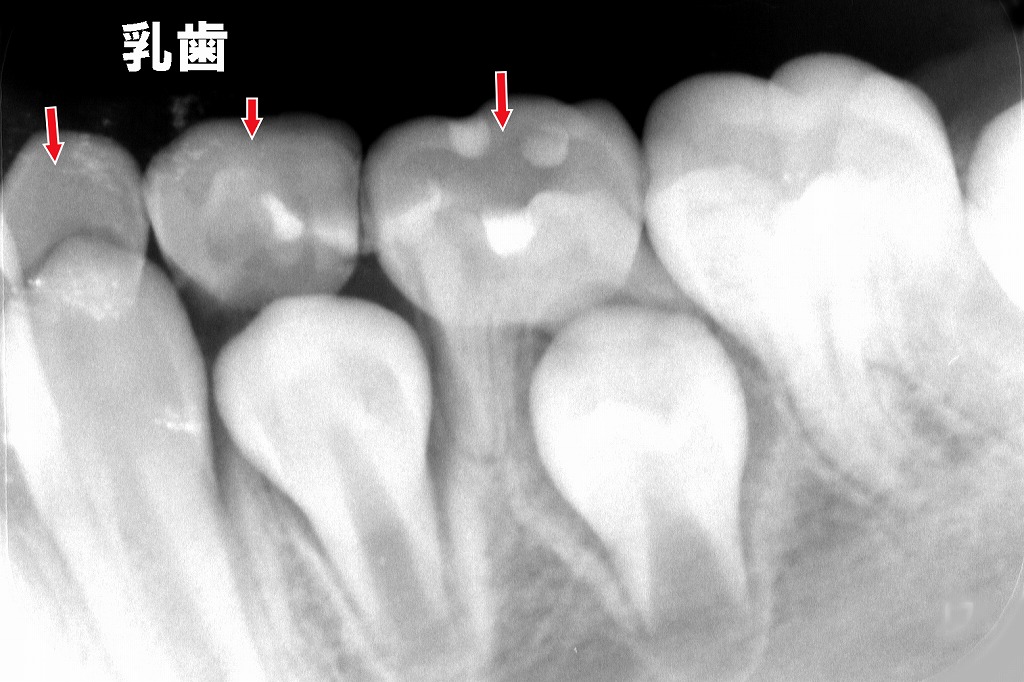

上顎第二小臼歯胚の先天欠損

上顎第二小臼歯胚が先天欠損しているため第二乳臼歯が抜けずに残存しています。

下顎第二小臼歯胚の先天欠損

下顎第二小臼歯胚が先天欠損しているため第二乳臼歯が抜けずに残存しています。

歯根吸収がだいぶ進んでいます。